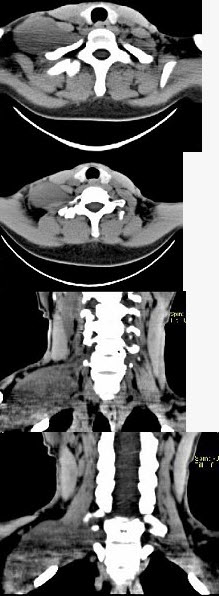

- 单项选择题女,47岁,下颈部触及一包块约五年余,CT如图所示,最可能诊断为()。

- C